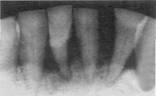

Radiografie periapicala pentru incisivii mandibulari

u se constata

- atritie, tartru si disparitia camerelor pulpare si canalelor radiculare prin dentina secundara de reactie indusa de atritie;

- parodontopatia marginala cronica profunda se manifesta radiologic prin rezorbtia (radiotransparenta) severa a septurilor interdentare si insertia precara a apexurilor in alveolele compromise;

examinarea radiologica si concluziile sunt facilitate de prezentarea aliniata, desfasurata a structurilor radiografiate inafara oricaror suprapuneri